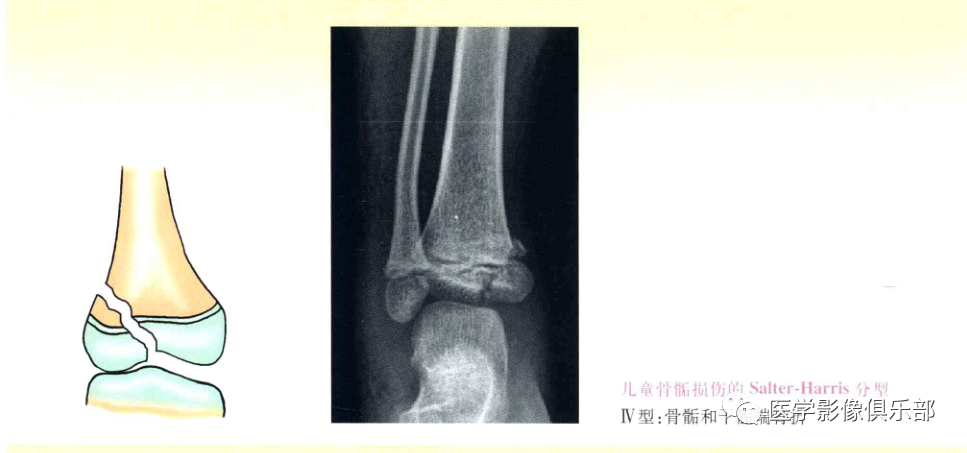

Ⅳ型:骨骺和干骺端骨折;

Ⅰ、Ⅱ型损伤,骨折线不经过骨骺,通常不造成生长发育障碍,Ⅲ、Ⅳ型累及骨骺,可造成生长阻滞和进行性畸形。

Ⅳ型:骨骺骨折伴干骺端骨骺分离。